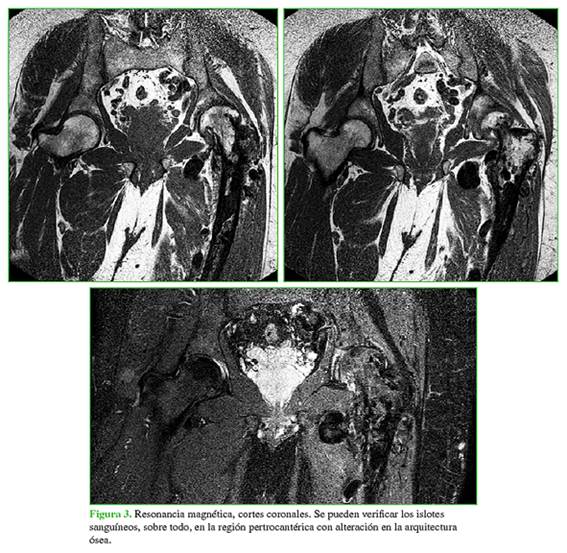

Se realizó una resonancia magnética en la que se constató la alteración de la arquitectura ósea por malformaciones vasculares en la cabeza, el cuello y la metáfisis femoral (Figura 3).

Se programó la colocación de una prótesis total de cadera híbrida, cotilo no cementado y tallo cementado, considerando la arquitectura del fémur proximal (Figura 1) y que, en la resonancia magnética (Figura 3), se observaban múltiples imágenes intraóseas correspondientes a fístulas arteriovenosas. La idea era disminuir el sangrado intracanal con el cementado.